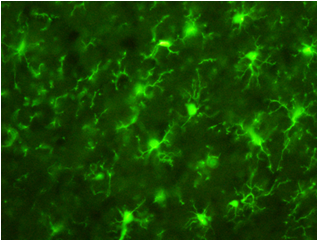

数据提供:创价大学理工学部中嶋老师

样本:大鼠(左)以及小鼠(右)大脑皮质冰冻切片

一抗:抗Iba1,山羊多克隆抗体(1:250)

二抗:Alexa Fluor488标记抗山羊IgG